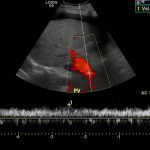

- Heterogeneous hypoechoic lesion in the periphery of the right hepatic lobe measuring up to 5.5 cm without internal vascularity

- Abscesses should not have internal vascularity (but remember that necrotic neoplasms may not have internal vascularity either)

- Watch out for associated complications including rupture into the peritoneal cavity and venous thrombosis